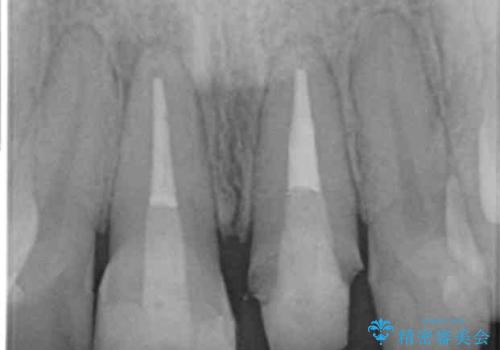

- 長年気になっている前歯の見た目を改善したいと来院されました。

両側の前歯に根尖性歯周炎を認めたため根管治療を行ったのち、ジルコニアクラウンを用いた審美性の改善を計画します。